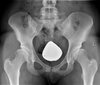

Oturma pozisyonunda uzun süre kalmak, kalça bölgesinde ağrıya neden olabilecek birçok faktörü barındırır. Özellikle kas zayıflığı, vücudun dengesini bozarak eklemlere aşırı yük bindirebilir. Kaslar zayıf olduğunda, eklemler üzerindeki yük artar ve bu durum zamanla ağrıya yol açabilir. Ayrıca, hareketsizlik dolaşım bozukluklarına neden olabilir; kan akışının yavaşlaması, dokuların oksijen ve besin alımını azaltarak ağrı hissine sebep olur.

Dolaşım bozuklukları, kanın yeterince pompalanamaması veya akışkanlığının azalmasıyla ortaya çıkar. Bu durum, kalçadaki kas ve dokuların beslenmesini olumsuz etkileyerek, ağrı ve rahatsızlık hissine neden olabilir. Ayrıca, damarların sıkışması veya iltihaplanması da benzer sonuçlar doğurabilir.

Uzun süre oturmak, sıklıkla postür bozukluklarına yol açar. Yanlış oturma pozisyonları, omurga ve kalça hizasını bozarak kaslarda dengesizlik yaratabilir. Bu durum, zamanla kasların aşırı gerilmesine veya zayıflamasına neden olarak kalça ağrısına yol açabilir. İyi bir oturuş pozisyonu, bu tür sorunların önlenmesine yardımcı olabilir.